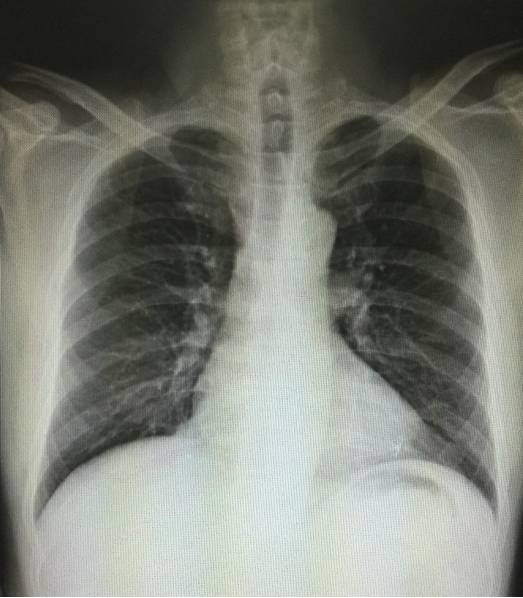

胸片(术前1月):

随访半年胸片(2015-4-1):